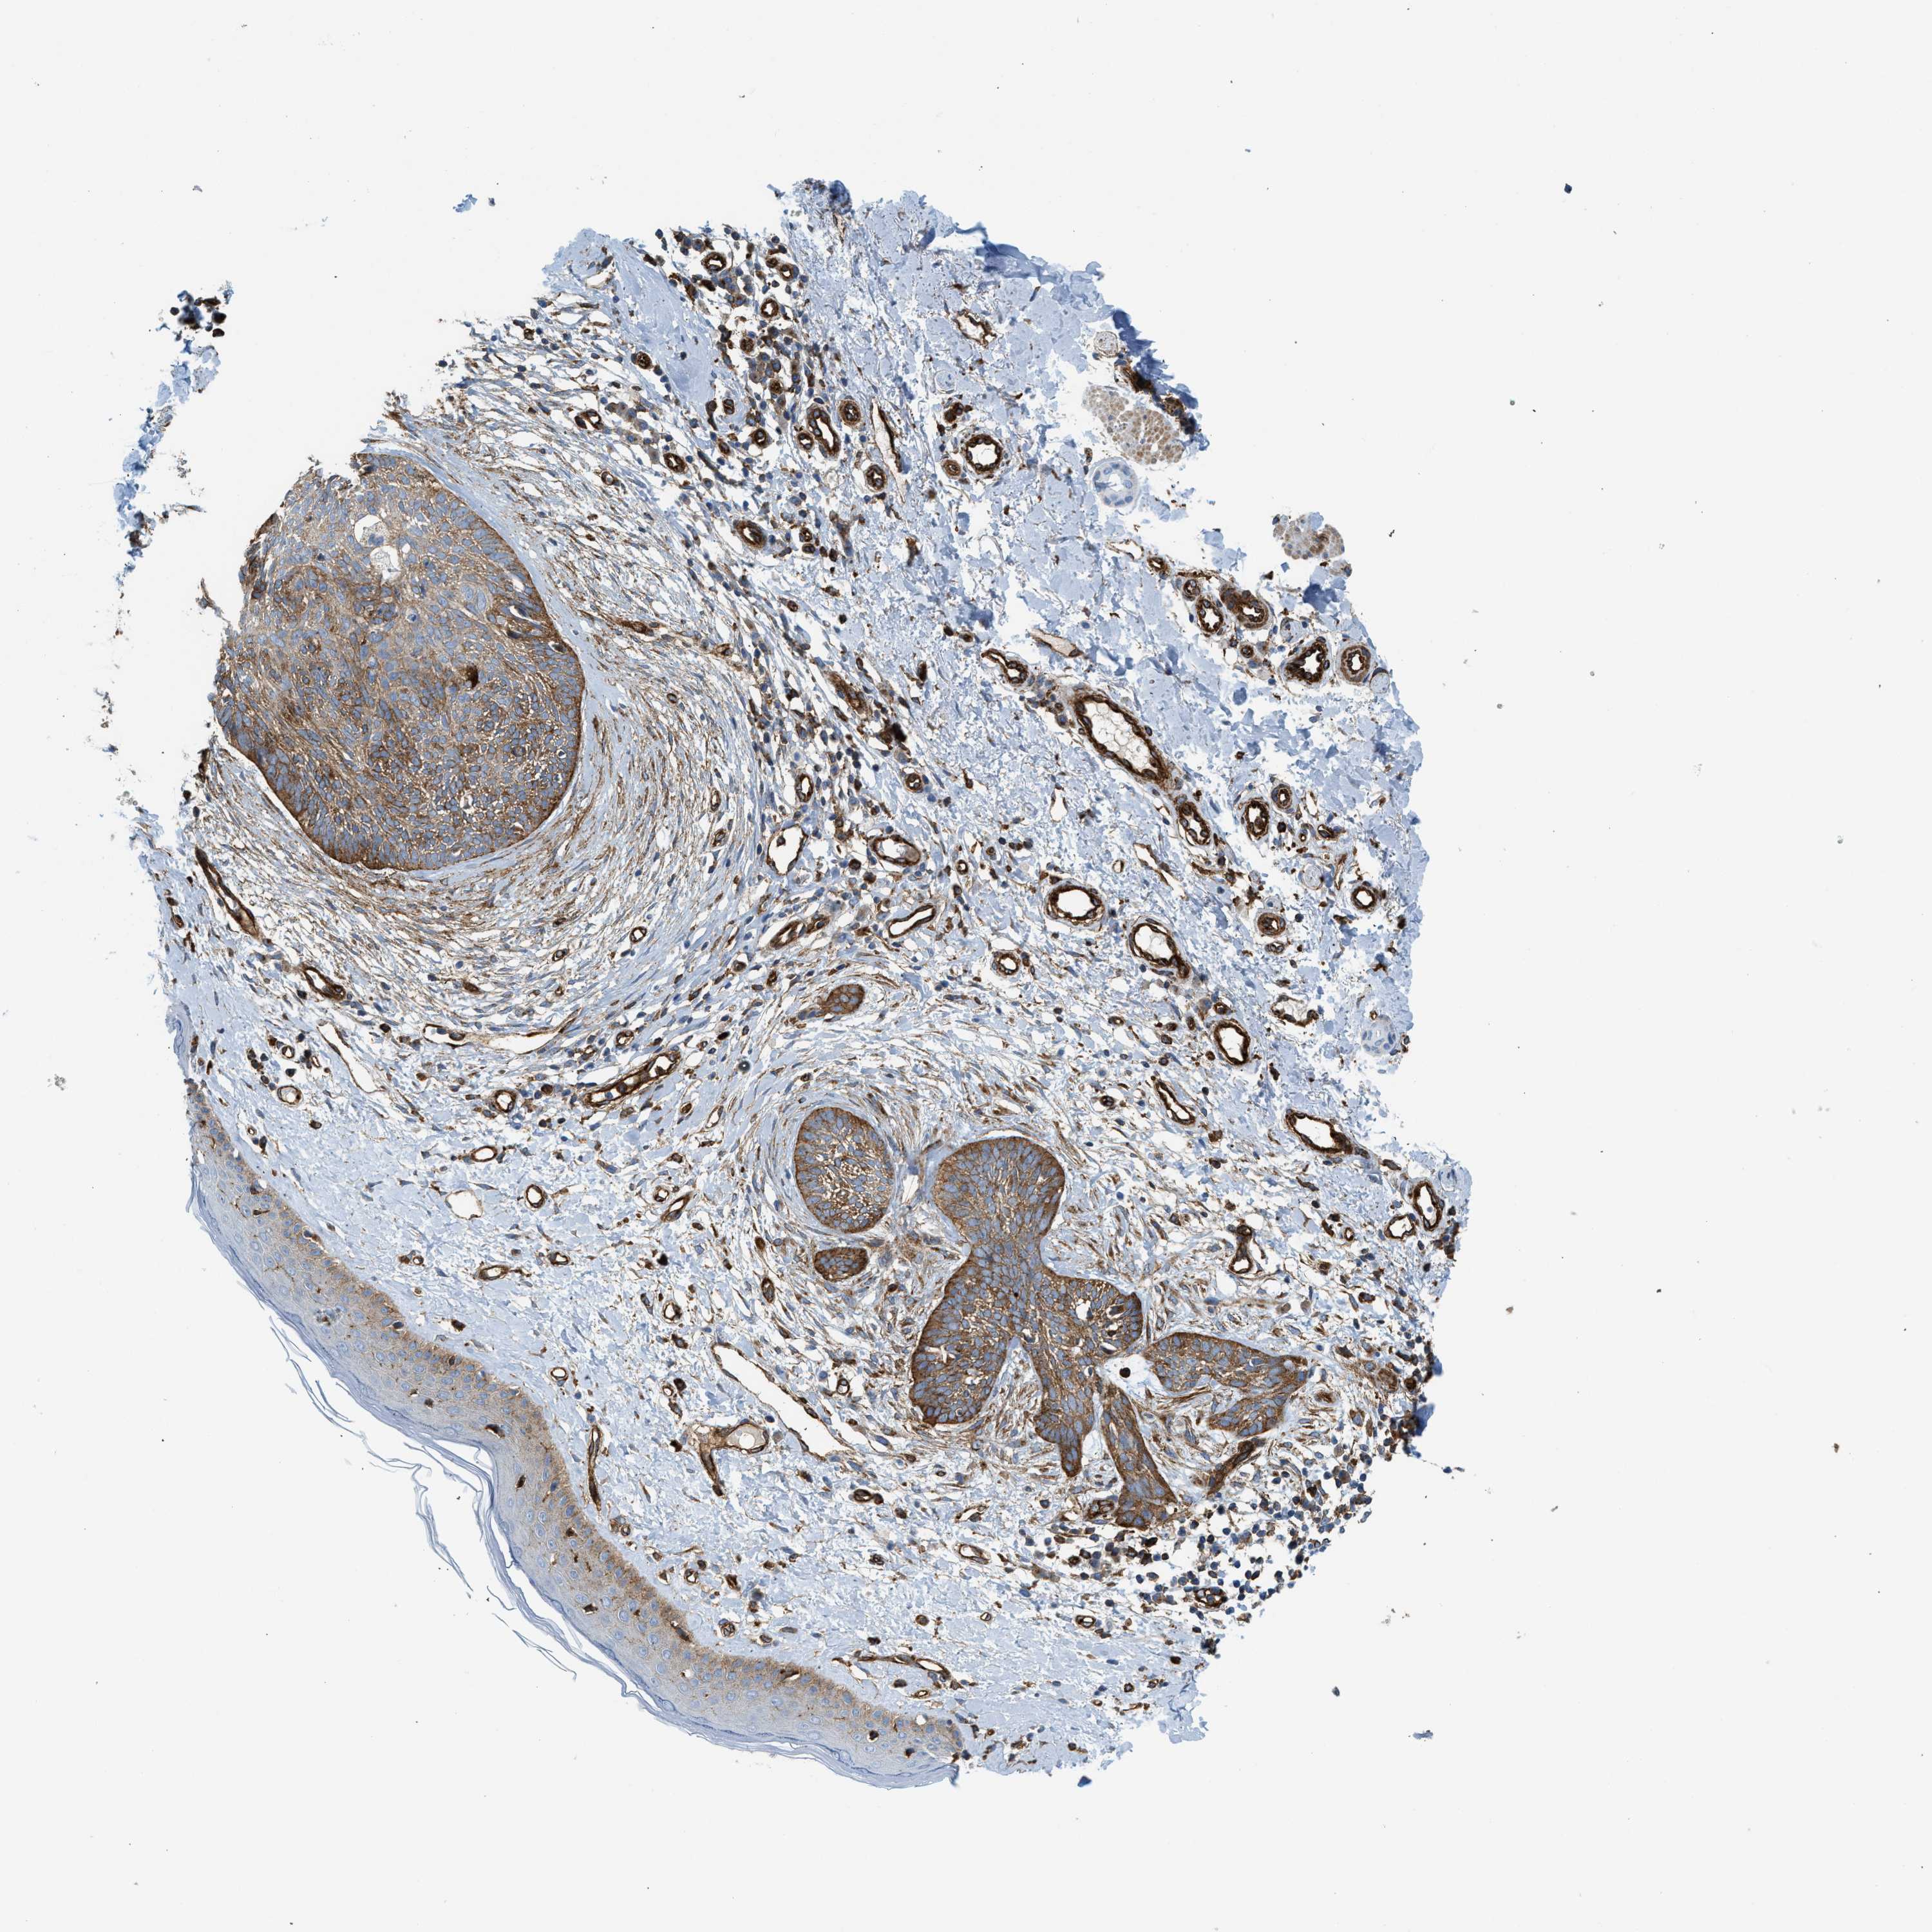

SKIN CANCER - Protein expressioni

A mouse-over function shows sample information and annotation data. Click on an image to view it in a full screen mode. Samples can be filtered based on level of antibody staining by selecting one or several of the following categories: high, medium, low and not detected. The assay and annotation is described here.

Antibody stainingi

Antibody staining in the annotated cell types in the current human tissue is reported as not detected, low, medium, or high, based on conventional immunohistochemistry profiling in selected tissues. This score is based on the combination of the staining intensity and fraction of stained cells.

Each image is clickable and will lead to virtual microscopy that enables deeper exploration of all samples and also displays staining intensity scores, fraction scores and subcellular localization as well as patient and tissue information for each sample.

Antibody HPA013606

Antibody HPA017964

Antibody CAB015334

Antibody CAB016402

Staining

High

Medium

Low

Not detected

Intensity

Strong

Moderate

Weak

Negative

Quantity

>75%

75%-25%

<25%

None

Location

Nuclear

Cytoplasmic/membranous

Cytoplasmic/membranous,nuclear

Squamous cell carcinoma in situ, NOS

Squamous cell carcinoma, NOS

Squamous cell carcinoma, metastatic, NOS

Basal cell carcinoma

Adnexal tumor, benign